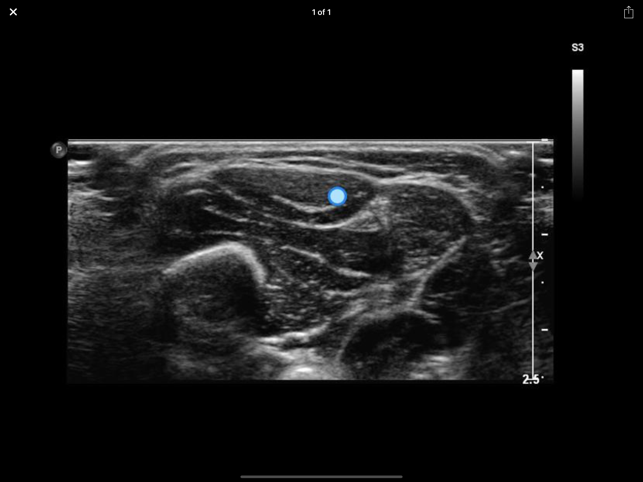

• Improve your skills in identifying muscles and neighbouring structures using ultrasound! • Instructive ultrasound cross-sectional images and videos• Plus: cross sections, scouts and the option for individual annotations• Use it as a Point-of-care APP on your smart phone or as a reference APP for anatomical studies. • Online content for quick reference and updates. Download option for permanent availabilityEntwickler App: Quickbird Studios GmbH, www.quickbirdstudios.comEntwickler Content: Child & Brain GmbH, www.childandbrain.com